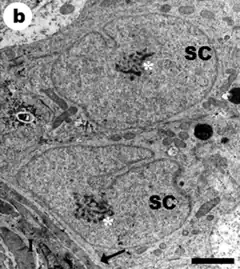

Con el microscopio electrónico, la célula de Sertoli (SC) muestra un núcleo celular con indentaciones y escotaduras en su membrana. La cromatina tiene gránulos dispersos y un nucléolo grande y central.

El citoplasma de la SC es abundante y con morfología cambiante, lo que hace difícil establecer las dimensiones mediante morfometría. En el ratón se ha estimado una longitud vertical (eje centrípeto) de 70-90 micrómetros (μm).[12]

Contiene numerosos orgánulos por lo que su aspecto es más oscuro (electrodenso). Es abundante en mitocondrias, lo cual indica el alto grado de actividad metabólica que posee la célula.

El citoplasma de la SC presenta prolongaciones y pliegues que rodean a las espermatogonias y sostienen a los espermatocitos. Los procesos laterales pueden ser de tres tipos: los cónicos que se extienden desde la superficie lateral cerca de su base; los de forma de copa y los procesos aplanados en forma de lámina, que se extienden entre las células germinales redondas.

Son notorios los complejos de unión intercelular (uniones estrechas), en el sector basal entre los procesos cónicos de las SC, que determinan la #Barrera hematotesticular con función de filtro.[13][11]